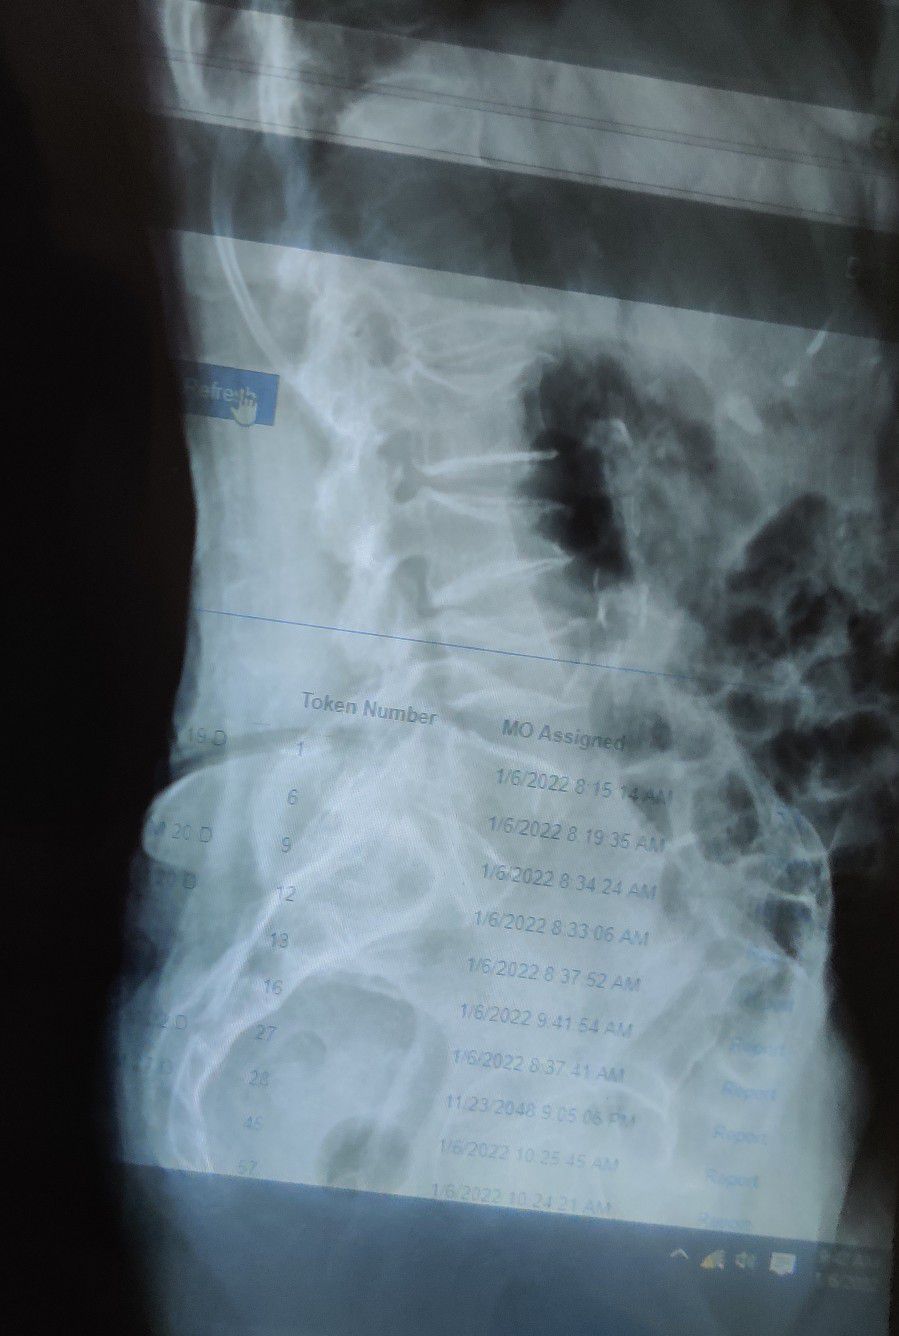

Osteoporotic Vertebral Compression Fracture

Ortho

Vertebrae

Osteoporosis

Few causes of osteoporosis are: Smoking Binge drinking Gastrointestinal disease Hyperthyroidism Autoimmune disease Coeliac disease Cushing's syndrome Hyperparathyroidism Low body weight

Management of osteoporosis: If you have osteoporosis, medical treatment can prevent further bone loss and reduce your risk of bone fractures. Treatment options for osteoporosis include dietary changes, exercise, lifestyle changes, falls prevention, supplements and medications.